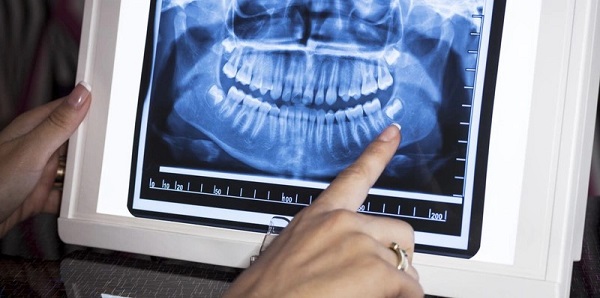

Đây là phương pháp chụp X quang được sử dụng để kiểm tra toàn bộ khoang miệng. Bằng cách sử dụng kỹ thuật chụp cắt lớp vi tính, nha sĩ có thể thấy rõ răng và mô xương. Trong quá trình chụp, bệnh nhân sẽ được bảo vệ bằng áo chì và cố định trên máy để thu được hình ảnh sắc nét của răng và xương hàm dưới.

Hình ảnh Panorama răng là một công nghệ chụp X quang cho thấy rõ về xương hàm trên và dưới, các thành phần lân cận như khớp thái dương hàm, xoang mũi. Kỹ thuật này cũng cho phép bác sĩ nhìn thấy toàn bộ hai cung răng trên một phim giúp chẩn đoán nhiều loại bệnh lý răng miệng như răng mọc lệch, răng mọc ngầm, u nang, áp xe và tổn thương xương hàm.

Ưu điểm của kỹ thuật Panorama răng là thời gian chụp nhanh, hình ảnh chất lượng cao, an toàn và phù hợp với mọi đối tượng, bao gồm cả trẻ em – nhóm khách hàng khó chụp X quang bằng các phương pháp truyền thống. Tuy nhiên, điểm trừ của phương pháp này là không phát hiện được những vấn đề như lỗ sâu răng, gãy xương, nhiễm trùng,…

Sau khi chụp X quang, bác sĩ sẽ xem và đọc kết quả. Họ sẽ giải thích cho bạn về các vấn đề được phát hiện và trả lời những câu hỏi liên quan đến sức khỏe răng miệng. Nếu bạn có bất kỳ câu hỏi nào về kết quả chụp X quang, đừng ngần ngại yêu cầu giải thích chi tiết hơn về tình trạng của răng miệng và các lựa chọn điều trị.